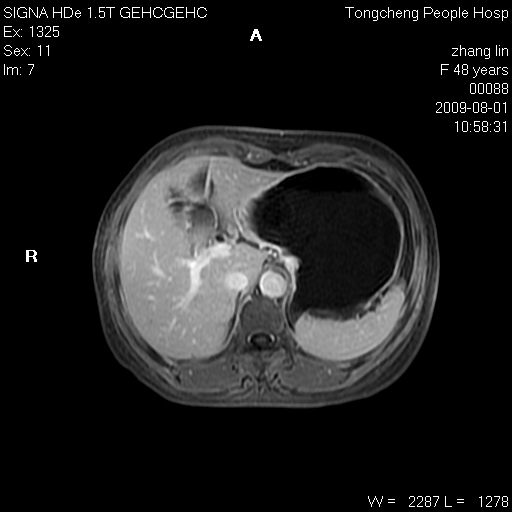

女,48岁。健康体检,彩超发现右肾占位性病变。平素健康。

临床诊断:右肾占位性病变,性质待定(囊肿?肿瘤?)。

上中腹部mr平扫+增强扫描,图像如下:

右肾上极见一类圆形病灶,t1wi呈等信号t2wi呈等高混杂信号,三期增强无强化,边界清---考虑囊肿出血。

同反相位均表现为等信号,病变无强化,考虑含蛋白的囊肿可能,弥散加权相或许有些帮助,